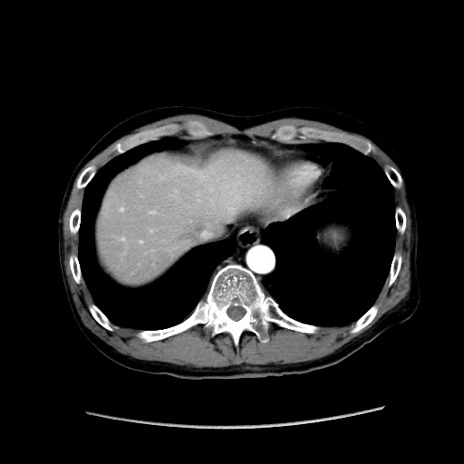

症例37(横断像)

【症例】40歳代 男性

【主訴】腹痛

【現病歴】4時間ほど前に電車に乗車中に臍部上より腹痛出現。徐々に増悪し起立困難となり、救急外来受診。生ものは数日食べていない。今朝お雑煮を食べた。

【身体所見】BT 36.8℃、BP 117/84mmHg、HR 91/min、SpO2 97%、苦悶様、腹部:臍上部広範囲圧痛あり、反跳痛±

【データ】WBC 8100、CRP 0.03